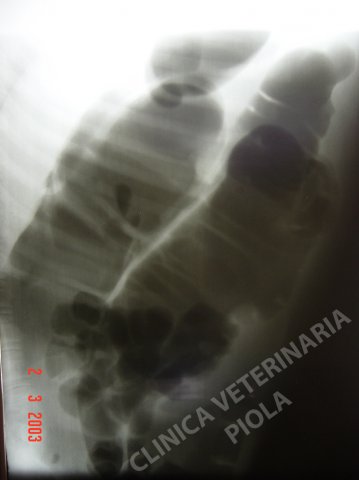

Ileo paralitico da sepsi